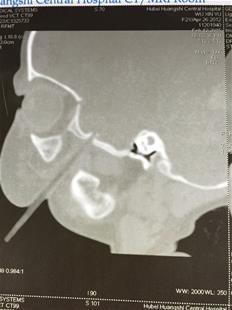

楚天都市报讯 图为:小可儿头部CT可清晰看见一根筷子

该院口腔颌面外科主治医生谢三祥告诉记者,经三维重建CT检查发现,筷子斜穿透小可儿的左颊部直到颅底骨,万幸的是,这根筷子巧妙地与几乎所有面部血管擦身而过,穿透的都是软组织,没有大面积出血,口腔内也没有伤口。“若筷子刺穿大血管,或者插进大脑伤及脑干,她就非常危险了。”